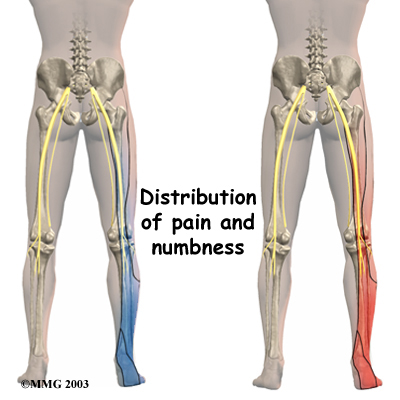

A herniated disc can press against a spinal nerve, producing symptoms of nerve compression. Nerve pain follows . It can be felt on the side of the upper thigh, in the calf, or even in the foot and toes.

Pressure on the nerve can also cause sensations of where the nerve travels down the lower limbs. If this happens, a person's reflexes slow. The muscles controlled by the nerve weaken, and sensation in the skin where the nerve goes is impaired.